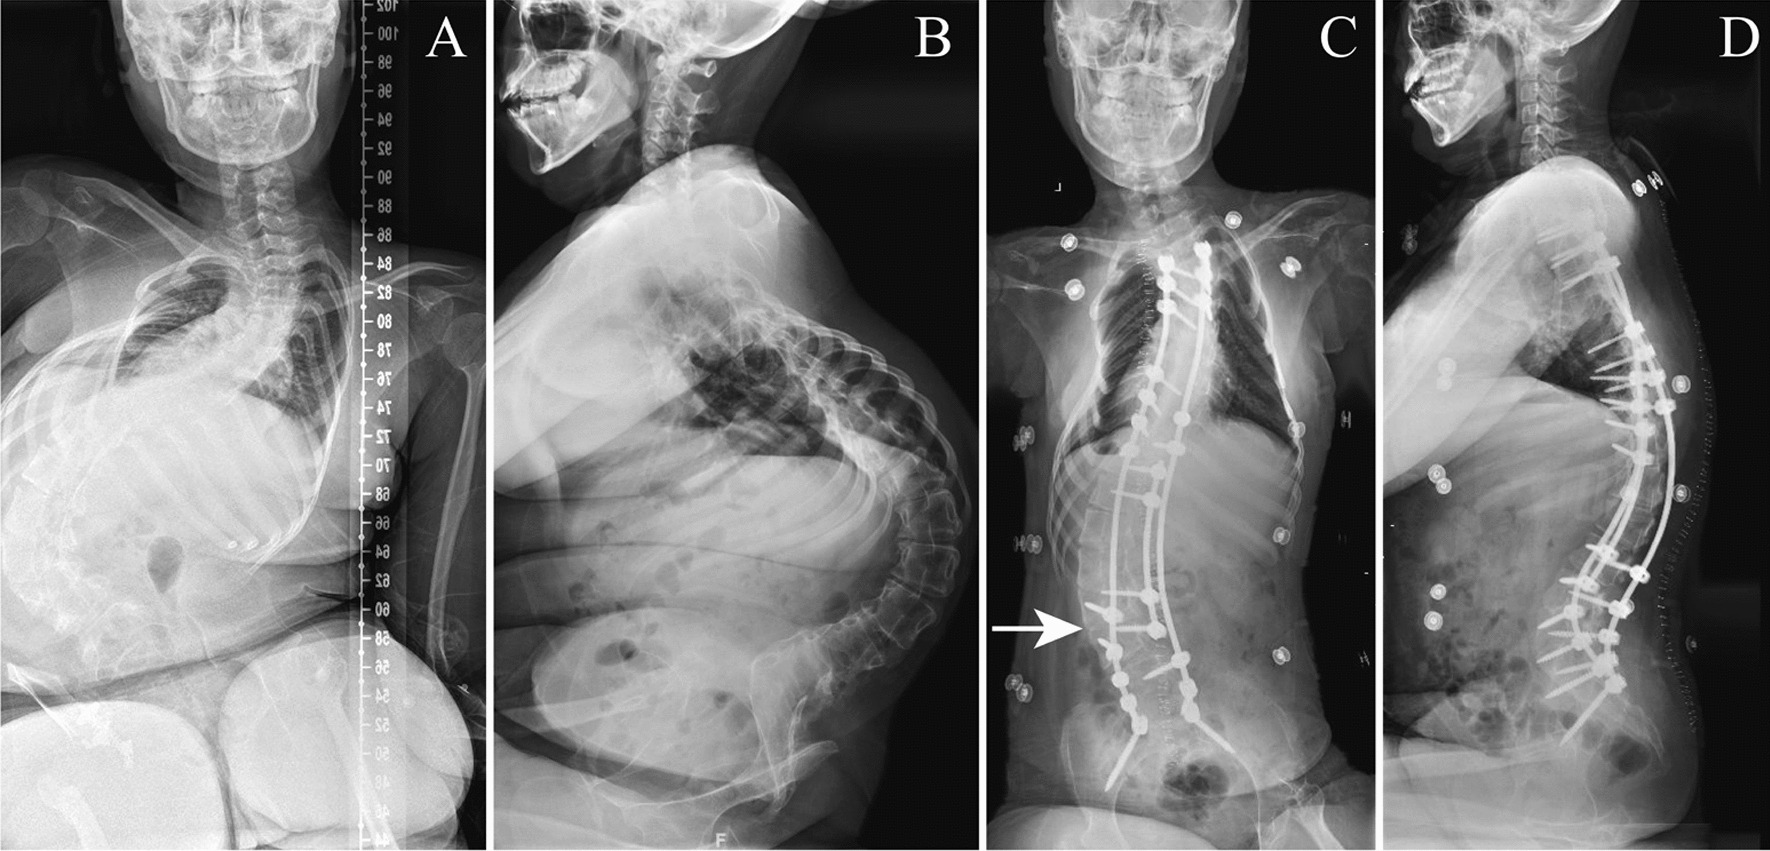

Fig. 2.

A 20-year-old female with SMA type II underwent posterior spinal fusion from T3 to pelvis. A, B Preoperative radiographs demonstrate a Cobb angle of 115.3° (T9–L4), pelvic obliquity of 28.9° and kyphosis of 102.4° (T4–L5). C, D Postoperative radiographs demonstrate good surgical outcomes with Cobb angle of 52.6° (T9–L4), pelvic obliquity of 11.6° and kyphosis of 21.3° (T4–L5). Unilateral interlaminar fenestration at L3–L4 level on the convex side (indicated by the white arrow) was performed during spinal fusion